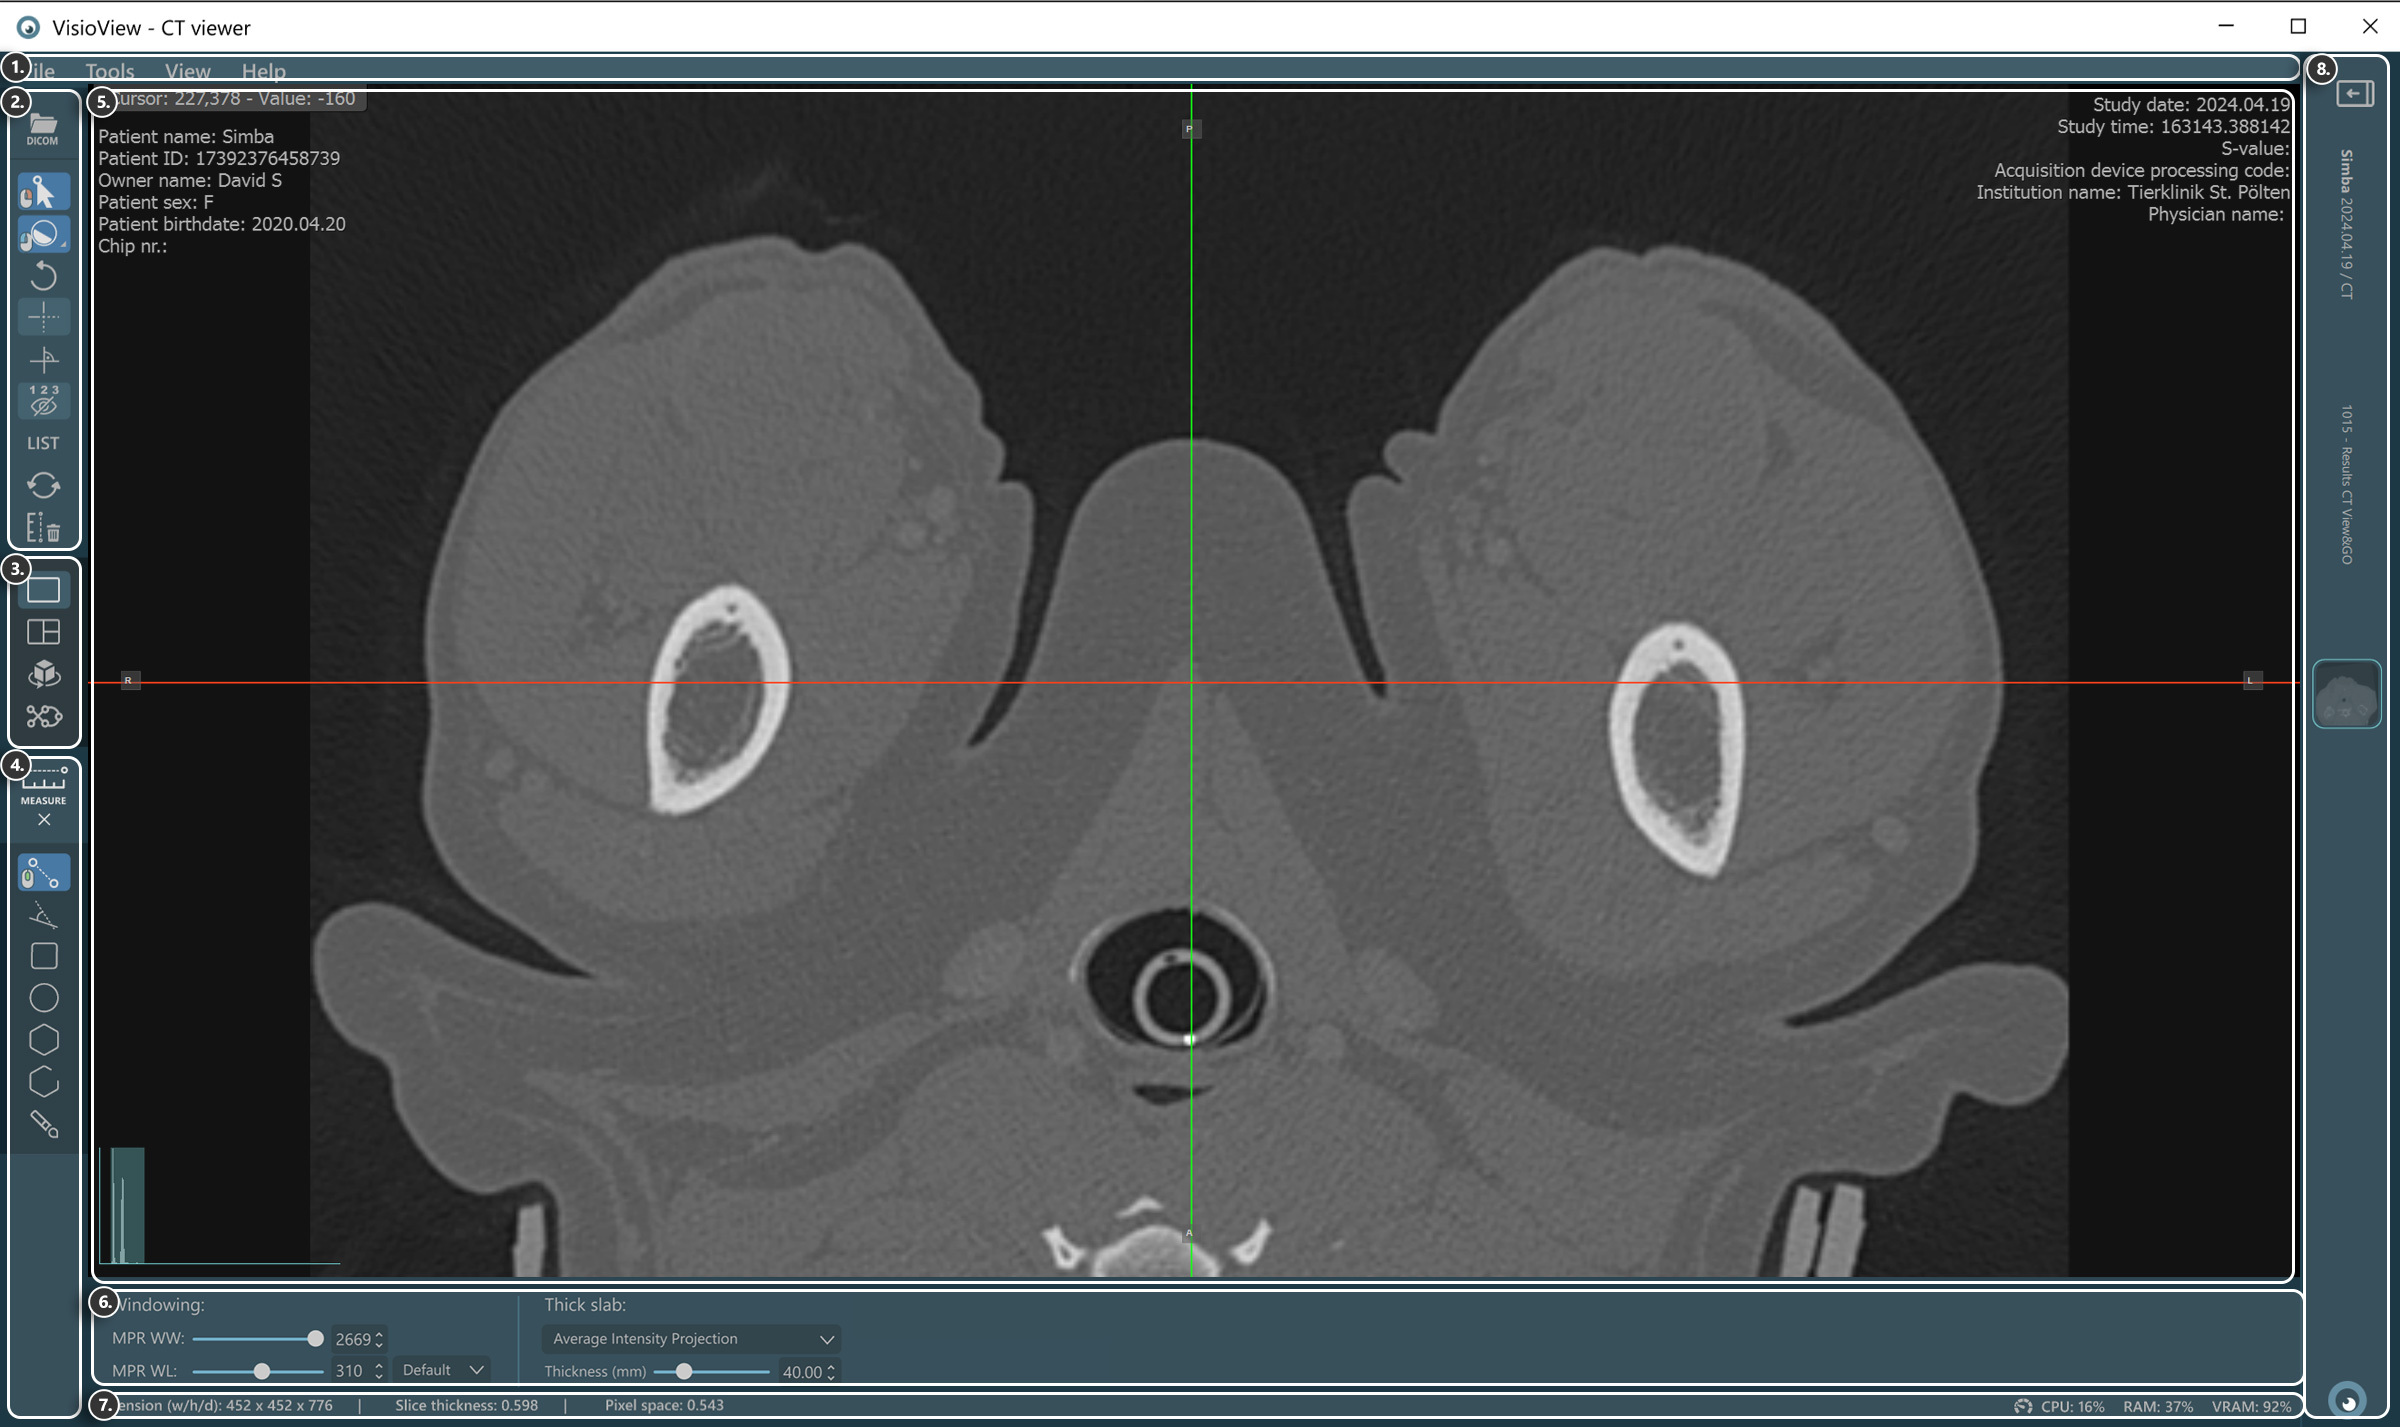

A VisioVIEW CT Megjelenítő szakaszai¶

A VisioVIEW CT Megjelenítő több szakaszból áll, amelyek mindegyike egy adott célra szolgál. Az alábbiakban az egyes szakaszok részletes leírása található.

DICOM-fájl betöltése

Elem kiválasztása

Ablakolási eszköz (Alapértelmezett, Dinamikus, vagy a meglévő ablakolási előbeállítások közül választva)

Nézetválasztó¶

Mérőeszközök¶

Megjelenítő terület¶

HU (Hounsfield-egység) pixelérték

Betegadatok

Ablakolási hisztogram eszköz

Szeletelők

Vizsgálati információk

Nézetbeállítások és opciók¶

Ablakolási beállítások

Vastag réteg beállítások

Információs sáv¶

DICOM-kép és felbontásinformáció

Teljesítmény- és erőforrás-használati információk